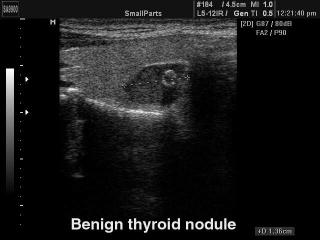

SonoAce-9900. Thyroid benign nodule, B-mode.